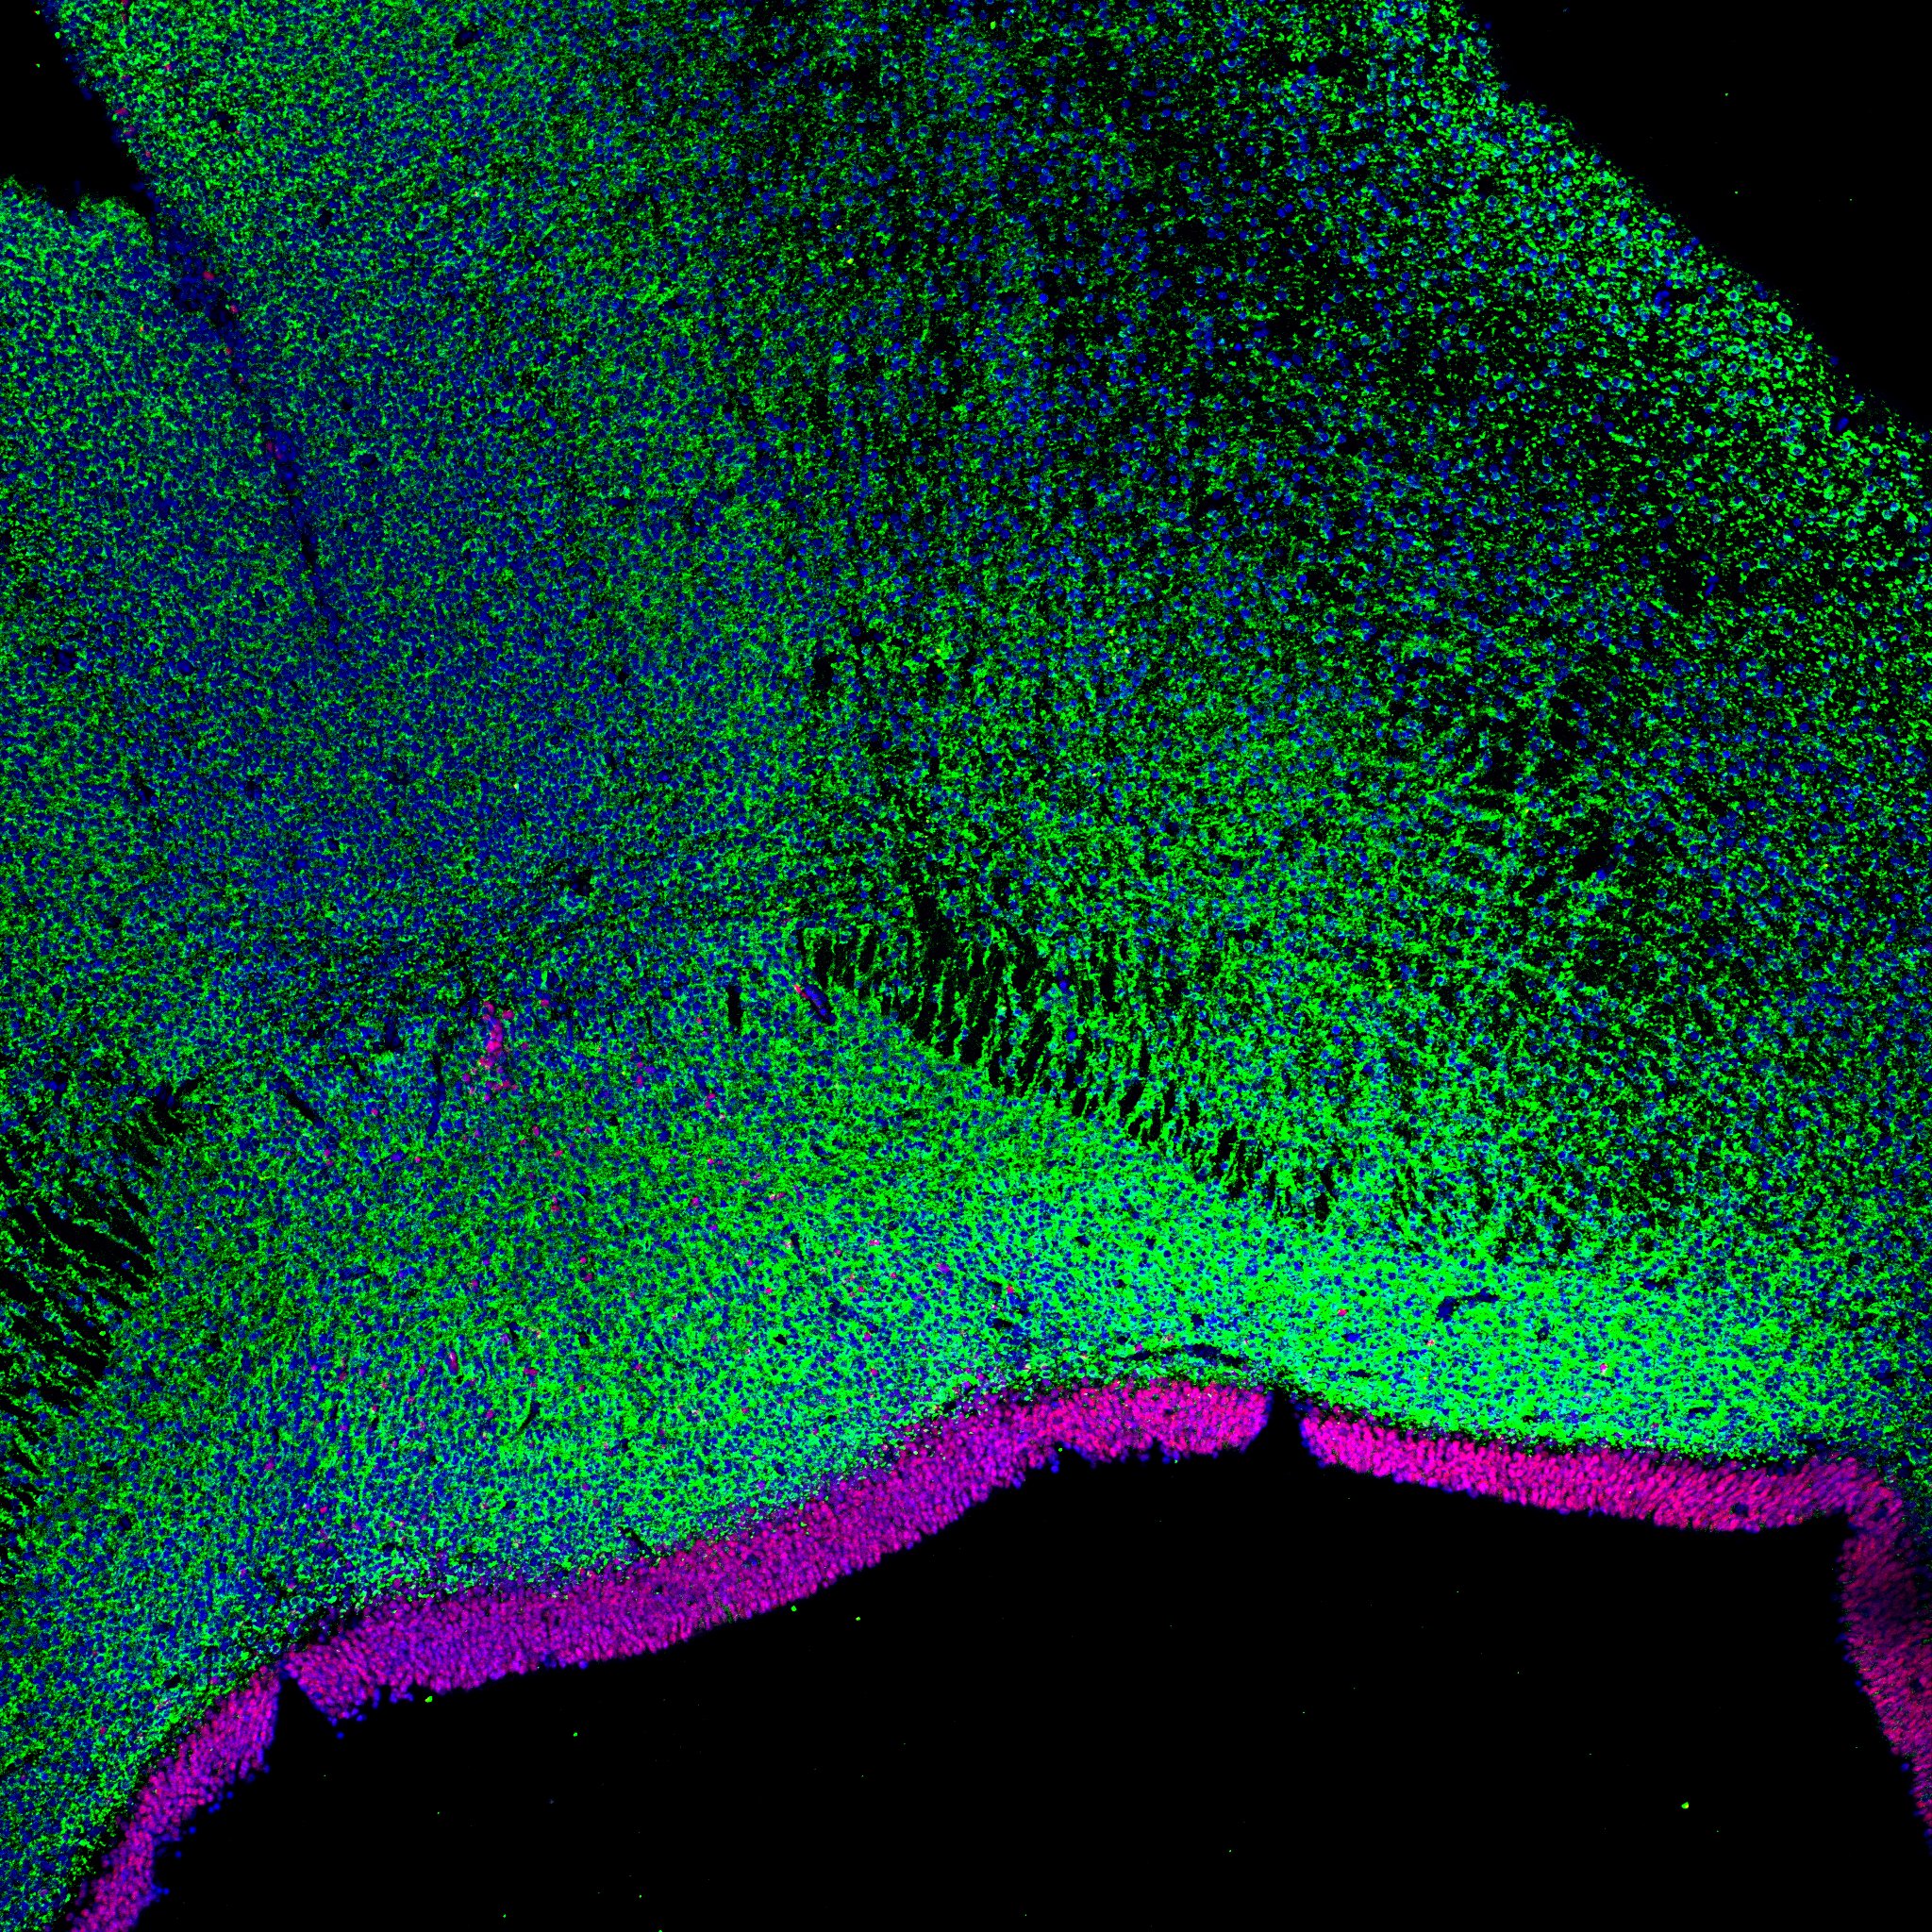

An anatomical analysis of the developing human midbrain from 6 post-conceptional weeks (PCW) to 22 PCW reveals increased tissue complexity, characterized by the emergence of dopaminergic nuclei, as highlighted by immunofluorescence analysis for tyrosine hydroxylase (TH).

MAP2

15PCW human midbrain

TH

Merged